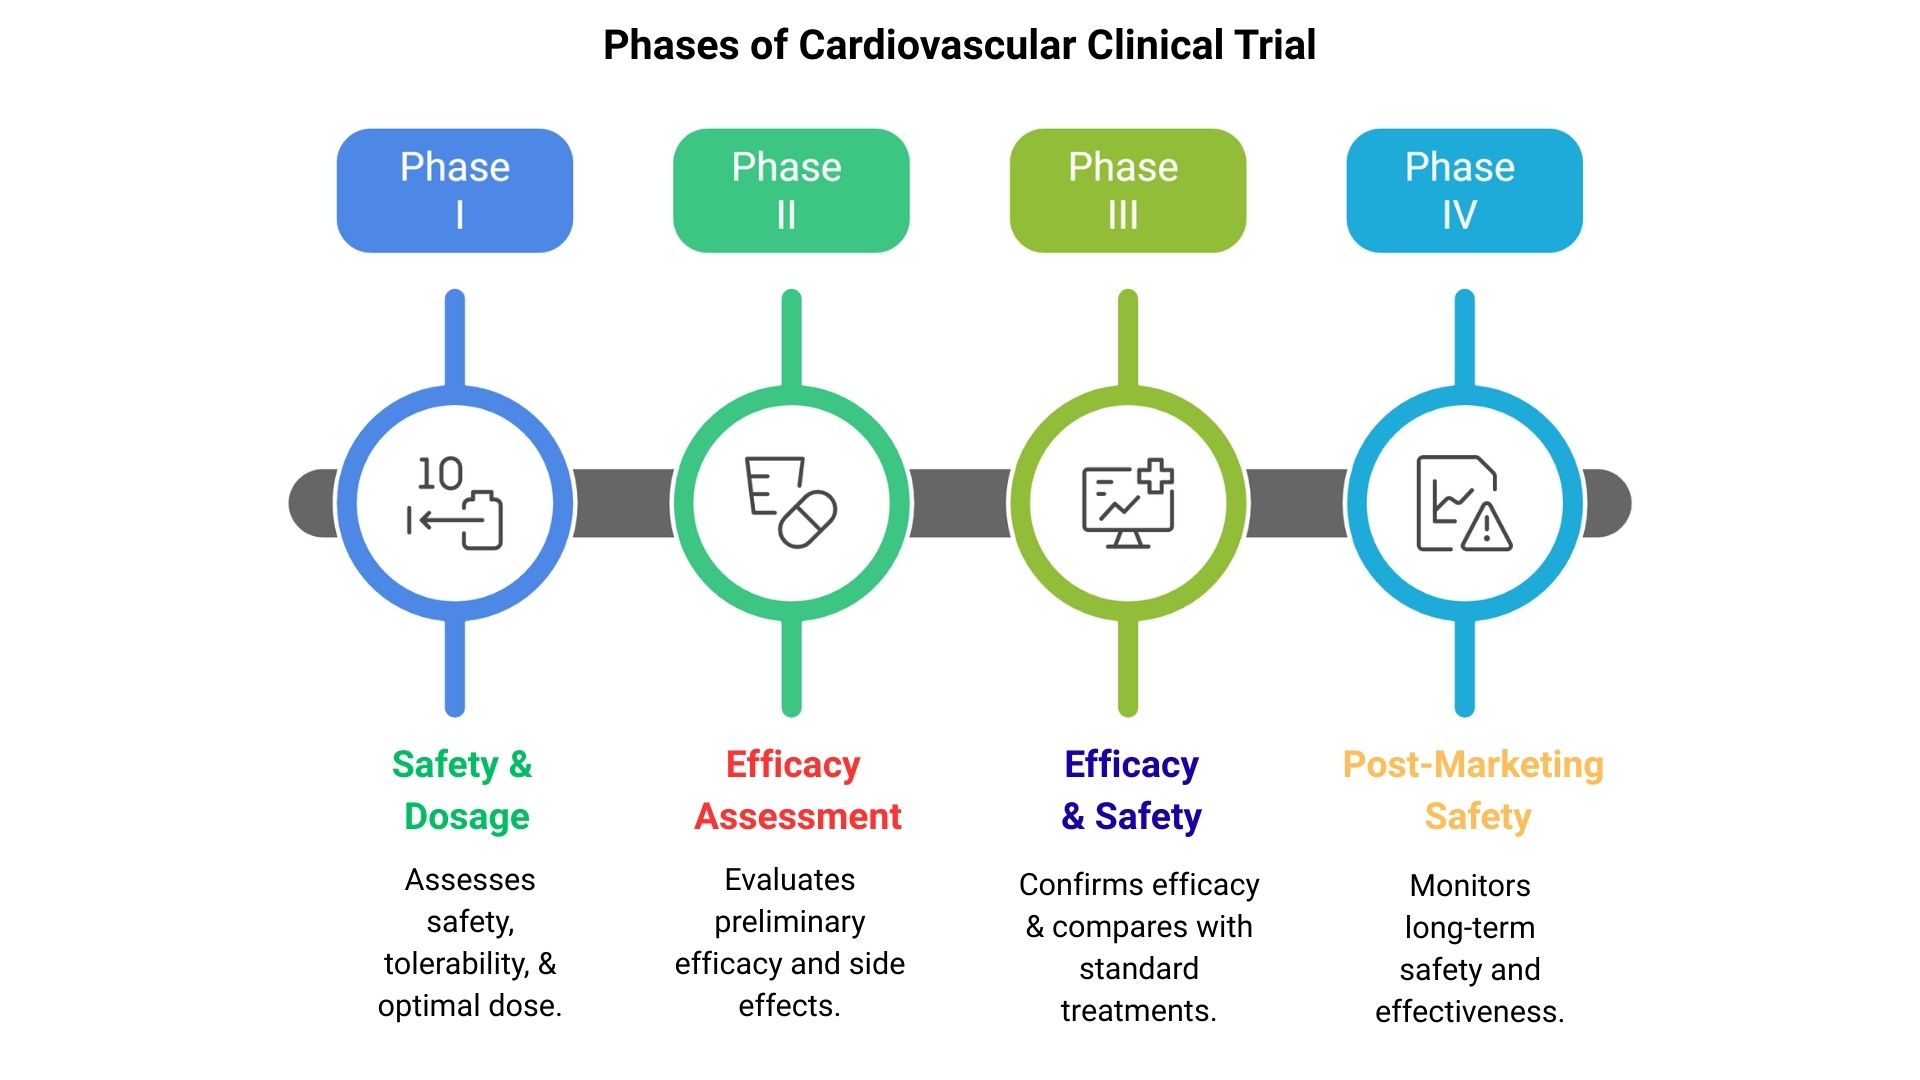

Cardiovascular clinical trials are critical for advancing therapies that improve heart and vascular health. These trials follow a structured progression, ensuring safety, efficacy, and regulatory compliance at each stage. By systematically evaluating treatments, researchers can deliver innovative solutions that address complex cardiovascular conditions. ProRelix Research, a distinguished clinical research organization, applies scientific rigor and regulatory expertise to support cardiovascular trials across all phases, ensuring patient-focused and data-driven outcomes.

This initial phase evaluates the safety, tolerability, and optimal dosage of a cardiovascular therapy in a small group of healthy volunteers or patients. Key objectives include identifying adverse effects and establishing pharmacokinetics.

Phase II trials expand to a larger patient population to assess preliminary efficacy and further monitor safety. This phase helps refine dosing regimens and study protocols for subsequent trials.

Phase III trials involve extensive patient cohorts to confirm efficacy, monitor side effects, and compare the therapy with standard treatments. Data generated in this phase are pivotal for regulatory approval.

After regulatory approval, Phase IV trials continue to monitor long-term safety, effectiveness, and potential rare adverse events in broader patient populations, ensuring ongoing therapeutic value.